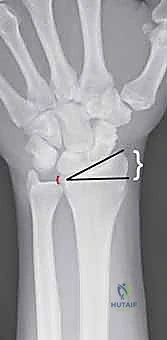

هو المعيار الذهبي الأساسي. يتم أخذ صور من زوايا متعددة (أمامية خلفية، وجانبية) لتحديد:

* موقع الكسر بدقة.

* مدى تفتت العظم.

* مدى انزياح العظم عن مكانه الطبيعي.

* تأثر سطح المفصل (الكسور داخل المفصلية).

3. استخدام جهاز الأشعة المرئية (C-Arm Fluoroscopy)

الخطوة السحرية في هذه العملية هي استخدام جهاز الأشعة السينية الحي (C-Arm). هذا الجهاز يتيح للدكتور هطيف رؤية العظام من الداخل في الوقت الفعلي على شاشة العرض. يتأكد الجراح من أن العظام عادت إلى مكانها المثالي وأن سطح المفصل مستوٍ تماماً.